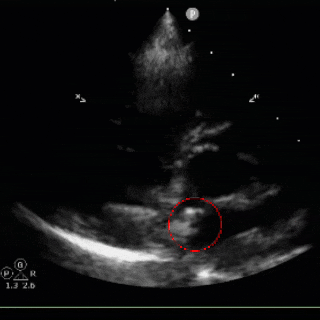

标准Valsalva:即刻可见微泡(中等量)

经胸右心声学造影:静息状态下,左侧肘静脉注射激活生理盐水(10ml),右心显影后,左心内未见明显微气泡,行Valsalva动作后右房增压状态,注射激活生理盐水(10ml),5秒后右心显影,左心内即刻出现10-15颗微气泡。

超声下鞘管通过卵圆孔

左盘展开

输送系统整体回撤使左盘贴靠房间隔